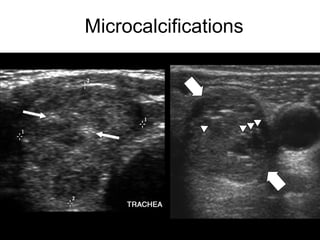

• Microcalcifications

Microcalcifications

Ultrasound • Hypoechoic • Increasedcentral vascularity • Incomplete halo • Microcalcifications • Irregular borders • Taller than wide (transverse view) • Suspicious lymph nodes • Hyperechoic • Peripheral vascularity • Complete Halo • Comet-tail • Large, coarse calcifications High Risk Features Low Risk Features